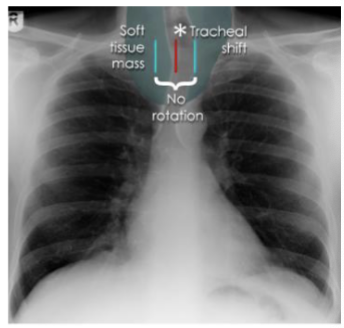

what is this?

tracheal displacement

what is this and what kind of scan

tracheal displacement, CT